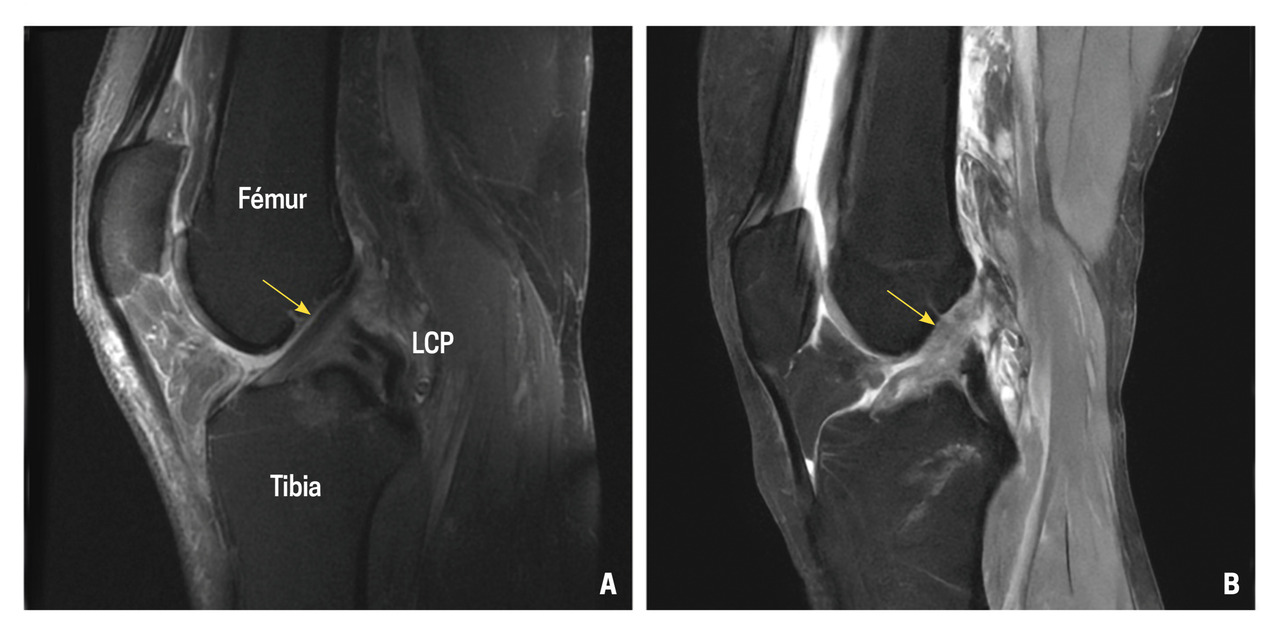

L’examen de choix permettant de confirmer la rupture du LCA est l’imagerie par résonance magnétique (IRM).3 Cependant, il n’y a pas lieu de réaliser une IRM pour toutes les entorses du genou. Cet examen ne doit normalement être réalisé qu’en cas de suspicion clinique de rupture du LCA après testing du genou par un examinateur spécialisé. L’IRM peut ainsi confirmer la suspicion diagnostique et identifier les éventuelles lésions associées4 telles que les lésions méniscales, du cartilage, et les contusions osseuses. Elle permet également de rechercher une atteinte des autres ligaments du genou (fig. 3).